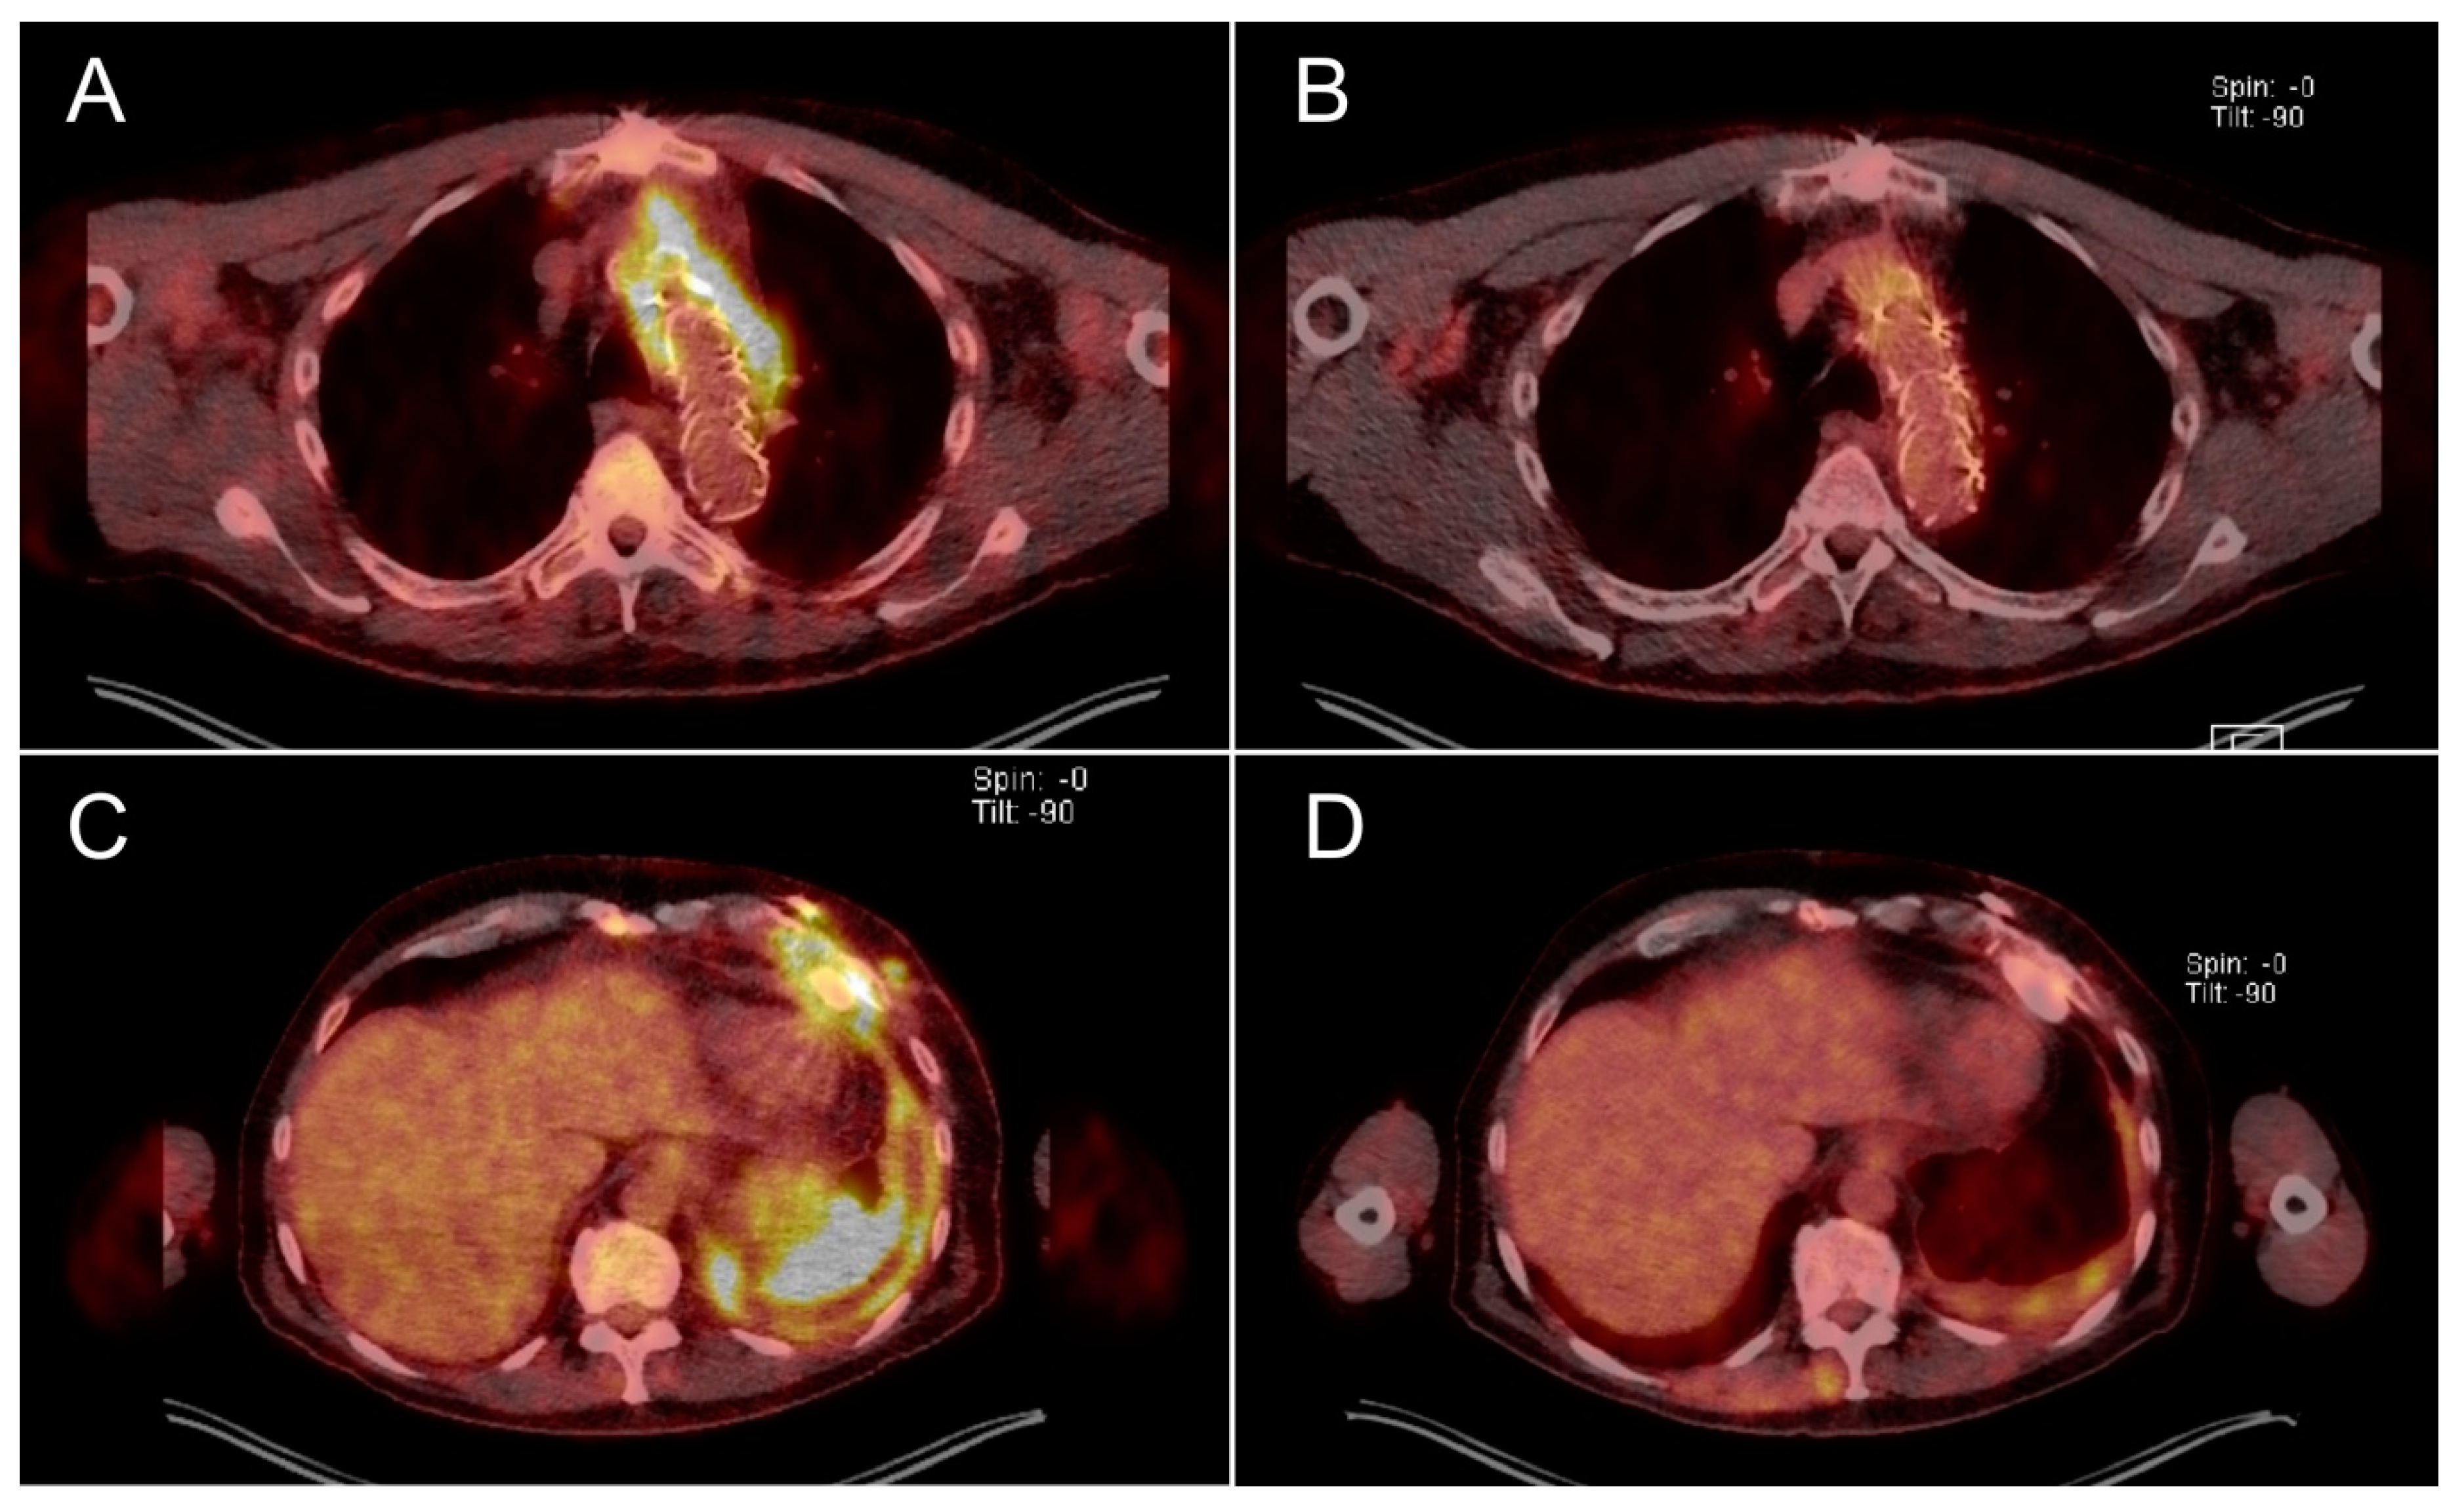

| Patient 2, 40 y.o., m. Lung infection during drug-induced immuno-suppression after heart transplantation. Transplantation: 23.07.2016. | Bronchial lavage Since 16.08.2016: pan-resistant K. pneumoniae. Rectal swab Since 27.06.2016: pan-resistant K. pneumoniae. | Infection with the pan-resistant bacteria | 1 × 108 pfu/mL Klebsiella phage KPV811 Klebsiella phage KPV15 | 29.08.2016–30.08.2016:

| 2000 mg ceftazidime, 600 mg linezolid, 500 mg avibactam intravenously twice per day. Inhalation of 1 MIU colistin three times per day. 2000 mg meropenem intravenously three times per day. 960 mg cotrimoxazole per os once per day. Tobramycin depending on drug concentration in blood (target concentration 2 mg/L). | K. pneumoniae not detected in bronchial lavage | Until present |